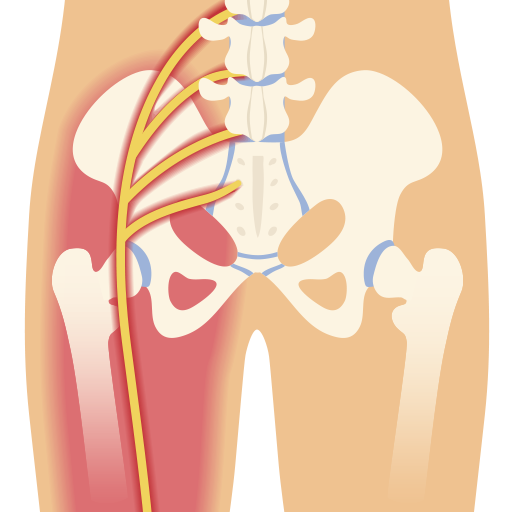

La ciática nerviosa es un conjunto de síntomas que indican la irritación o compresión del nervio ciático. Este nervio, el más largo del cuerpo, se extiende desde la parte baja de la espalda hasta las piernas. Los síntomas más comunes incluyen dolor, debilidad y entumecimiento a lo largo del trayecto del nervio. La ciática puede ser causada por diversas condiciones, y su tratamiento varía según la causa subyacente. ¿Qué es la ciática nerviosa? La ciática nerviosa se refiere a un grupo de síntomas que se producen debido a la irritación o compresión del nervio ciático. Estos síntomas pueden afectar la movilidad y la calidad de vida de la persona. Definición y generalidades La ciática se manifiesta a través de un dolor que comienza en la parte baja de la espalda y se irradia a lo largo del trayecto del nervio ciático, que se extiende por las nalgas y hacia las piernas. Esta afección no es una enfermedad en sí misma, sino un síndrome que resulta de problemas subyacentes que afectan al nervio. Algunos factores incluyen: Hernias de disco intervertebrales que pueden presionar el nervio. Estenosis raquídea que provoca un estrechamiento del canal espinal. Compresión causada por espolones...